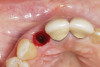

Fig 5. Atraumatic extraction without raising the flap, with the intention of minimizing bone loss, especially in the interproximal area.

Figure 5